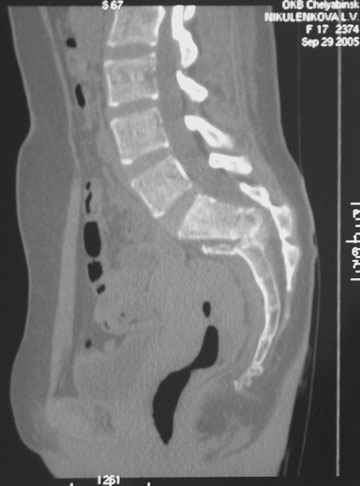

Травма 21.августа 2005г. На девочку в лесу упала береза. Доставлена в ближайшую ЦРБ. При поступлении установлен диагноз: Травматический шок 2-3 ст. Тупая травма живота. Забрюшинная гематома. Перелом костей таза с нарушением целостности тазового кольца. Перелом лонной и седалищной костей справа. Перелом поперечных отростков L3 - L5. Разрыв КПС справа. При поступлении выполнена диагностическая лапароскопия — выявлена обширная забрюшинная гематома. Было наложено скелетное вытяжение за бугристости обеих б/берцовых костей, больная уложена в гамак. Через неделю скелетное вытяжение демонтировано, гамак снят. Девочка уложена в положение «лягушки». Контрольные рентгенограммы через 4 недели после травмы. Заподозрен перелом дужки L5. Больная 26 сентября 2005 г. переведена в областную больницу в отделение детской ортопедии. При поступлении в локальном статусе: пальпация и перкуссия остистых и поперечных отростков L4-5 болезненная. Пальпация костей таза б/болезненная. С-м натяжения слабо положителен. Осевая нагрузка положительная. Движения в т/б суставах ограничены, болезненны. C-м прилипшей пятки отрицательный. C-м Ларрея и Варнейля отрицательный. Периферическая гемодинамика не нарушена.Неврологический статус: вторичная двусторонняя радикулопатия L5-S1. 29 сентября произведена компьютерная томография позвоночника и таза.

Судя по томограммам, радикулопатия может быть из-за компресии "конского хвоста" смещенным крестцовым позвонком, это хорошо видно на втором слева снимке. Если этот сегмент будет нестабилен и будет сохраняться неврологическая симптоматика, придется оперировать. Если неврологическая симптоматика уйдет и перелом стабилизируется, то можно обойтись без операции.